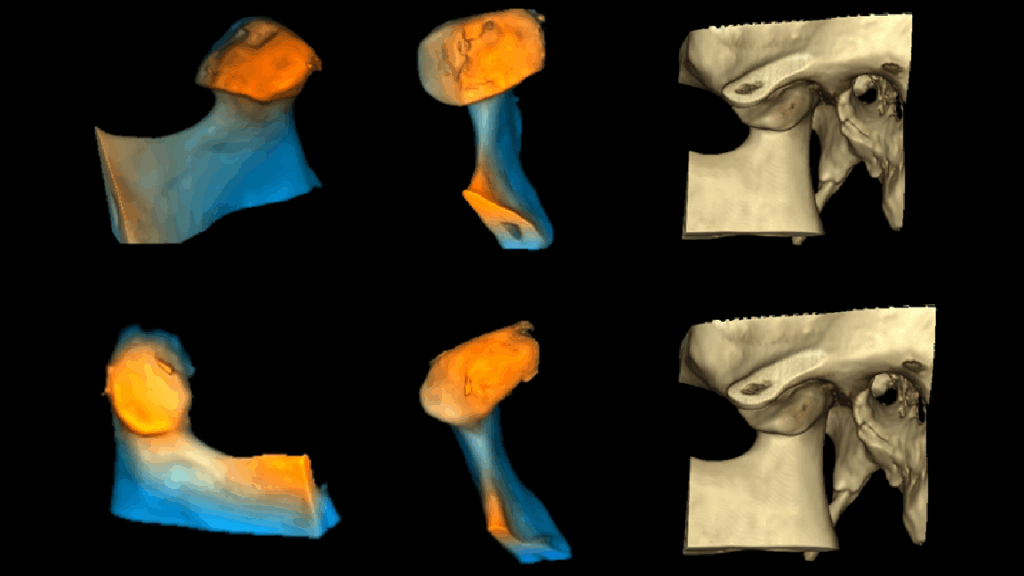

A la evaluación de la tomografía computarizada de haz cónico (FOV 10 X 10) se observa que ambos cóndilos presentan un aplanamiento marcado de los contornos, erosión de las corticales, así como la presencia de osteofitos. Asimismo, se observa el aplanamiento de la cavidad glenoidea bilateral y la disminución considerable de los espacios articulares. Finalmente, en la tomografía de boca abierta y cerrada se observa la disminución en el recorrido condilar bilateral, signos imagenológicos compatible con proceso degenerativo articular e hipomovilidad bilateral.

RECONSTRUCCIÓN 3D

Los principales signos hallados por medio del diagnóstico por imágenes son: esclerosis del hueso subcondral, erosión, aplanamiento de las superficies articulares, deformación en la superficie condilar, osteofitos y disminución del espacio articular 9,32,50 . La radiografía panorámica, es la primera herramienta para identificar cambios estructurales a nivel de la ATM; sin embargo, la agudeza con la que puede evidenciar estos cambios debe ser evaluada con Cuidado.

La TCHC permite observar los tejidos duros que componen a la ATM, pero tiene como limitante no reflejar a los tejidos blandos como el disco articular y músculos. La resonancia magnética (RM) permite la visualización de los tejidos duros y blandos que componen la ATM, especialmente el disco articular1,2. Ikeda señala que el uso combinado de TCHC y RM es sinérgico, permitiendo observar cambios en la posición condilar dentro de la fosa y cómo estos cambios se relacionan a las variaciones morfológicas en los tejidos duros y blandos de la estructura articular.